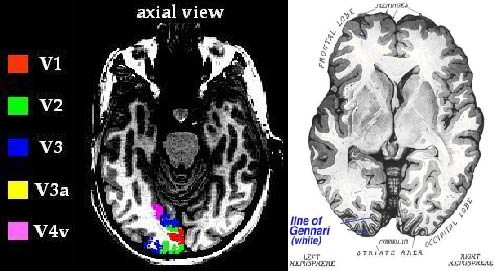

(a) (b)

Figure

6. (a) A sophisticated fMRI

scan outlining the primary visual cortex (V1) and other cortical regions (V2,

V3, V4). (b) Horizontal anatomical image of the brain showing the line of Gennari. An image as that produced in (a) only gives

relative values and hence it is not possible to quantitatively characterize the

location of the visual cortex.